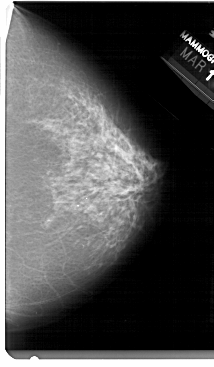

A_1480_1.LEFT_MLO

LEFT_MLO LINES 5491 PIXELS_PER_LINE 3076 BITS_PER_PIXEL 12 RESOLUTION 43.5 OVERLAY